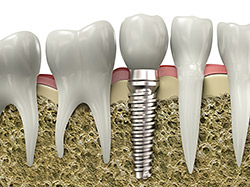

If your looking for Seattle, WA dental implants, you have come to the right place. If you have missing teeth, it is crucial to replace them. Without all your teeth, chewing and eating can destabilize your bite and cause you discomfort. When teeth are missing, your mouth can shift and even cause your face to look older. Implants are a great way to replace your missing teeth, and if properly maintained, can last a lifetime!

An implant is a new tooth made of metal and porcelain that looks just like your natural tooth. It’s composed of two main parts: One part is the titanium implant body that takes the place of the missing root, and the second part is the tooth-colored crown that is cemented on top of the implant. With periodontal treatment, you can smile confidently knowing no one will ever suspect you have a replacement tooth.

In addition to tooth replacement, Seattle, WA implants may be used to anchor dentures, especially lower dentures that tend to shift when you talk or chew. For patients with Seattle, WA removable partial dentures, implants can replace missing teeth so you have a more natural-looking smile.